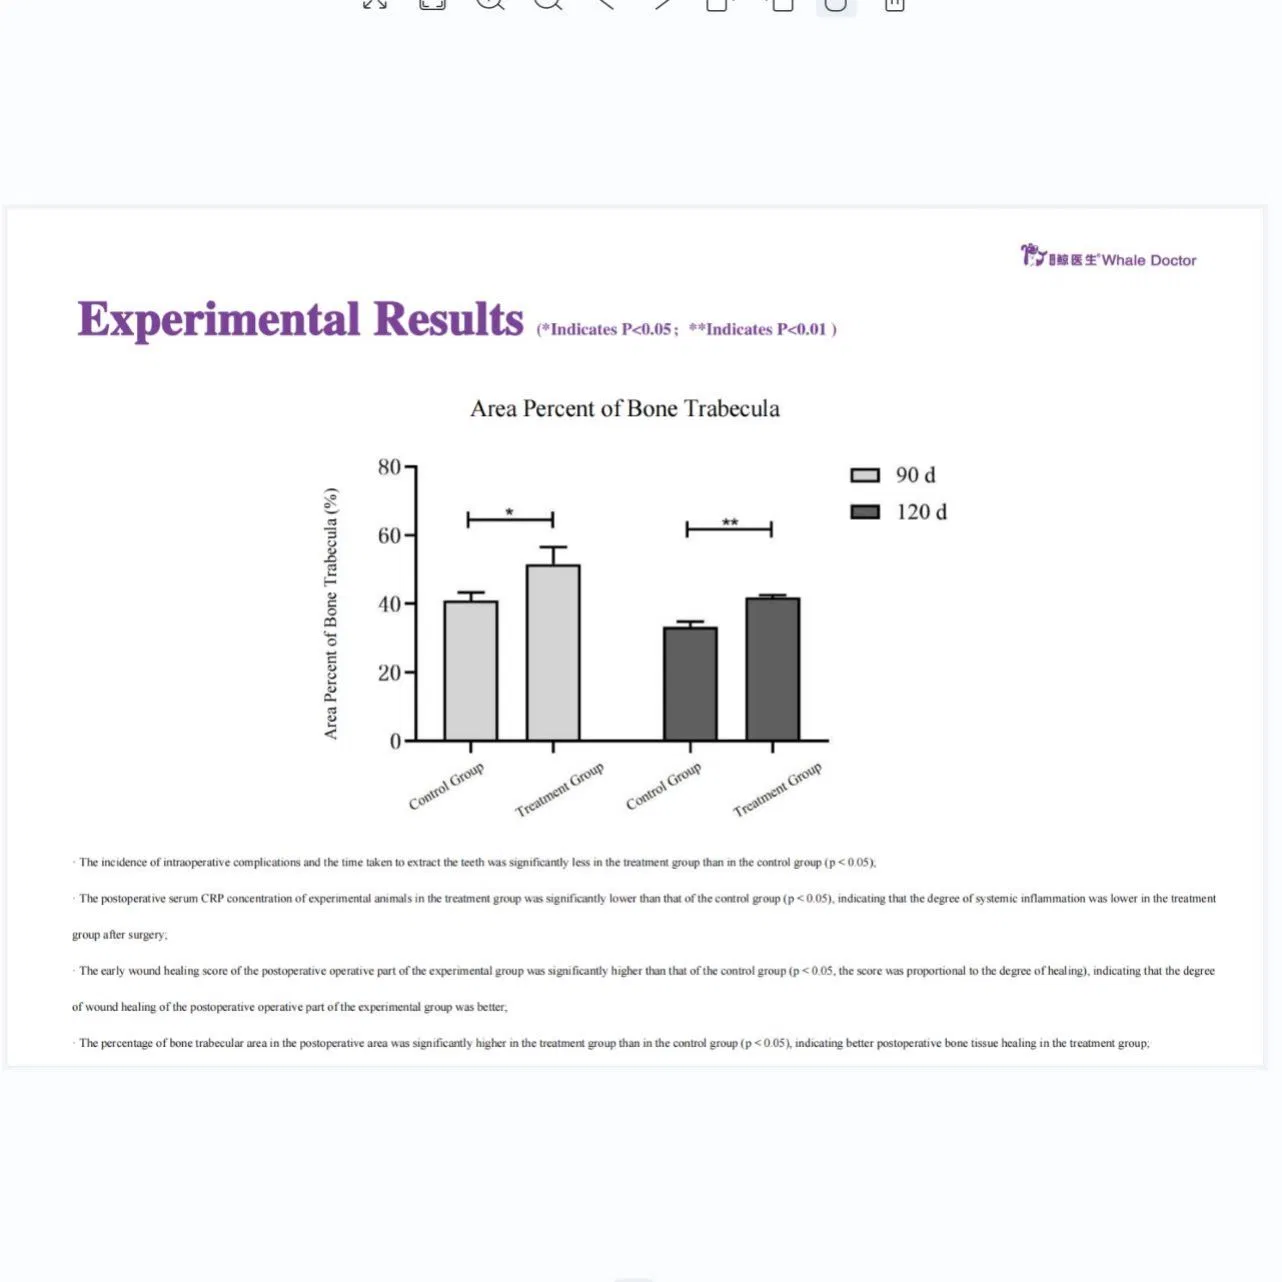

This study evaluated the effectiveness of state-of-the-art dental tools for veterinary use. The treatment group utilized the revolutionary Pneumatic Dental Elevator Kit. Critical factors observed included physiological parameters, intraoperative complications, extraction duration, and socket damage. Rigorous statistical analysis highlights the superior performance of these advanced tools.